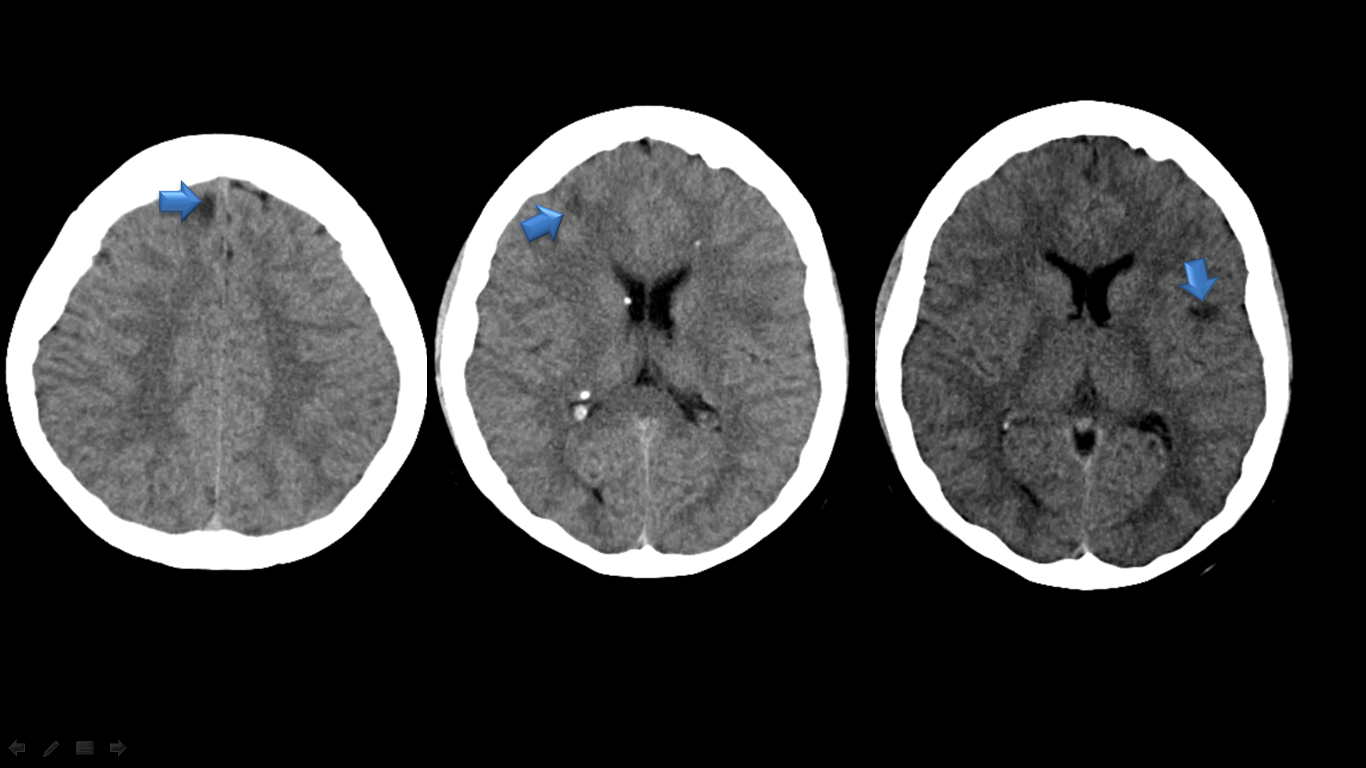

Cortical tubers and subcortical areas of junctional dysmyelination can be demonstrated clearly by mri, whereas small calcifications may be missed because of low contrast if the chosen sl. Tuberous sclerosis (tsc) is a rare genetic disease that causes benign tumors to grow in the brain and on other vital organs such as the kidneys, heart, eyes, lungs, and skin. 57 rows tuberous sclerosis complex (tsc) is characterized by the growth of. The results of the magnetic resonance imaging of three patients with proven tuberous sclerosis will be discussed.

More severe symptoms may occur when the tumors affect the normal function of a body organ. Brain lesions in tsc include: Skin, eyes, and nervous system). The tumors most often affect the brain, heart, skin, kidneys, eyes and lungs.